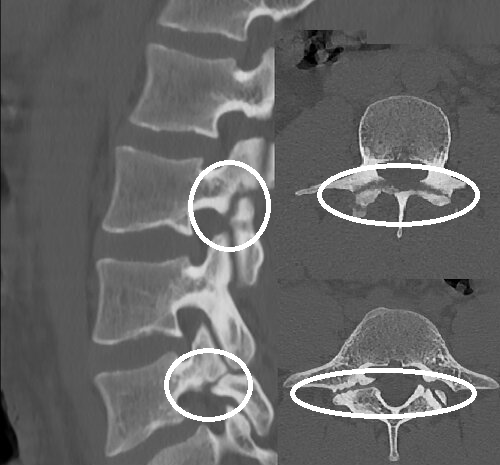

И на представленных снимках это так - спондилолиз (деффект) есть, а спондилолистеза (смещения) нет:

Спондилолиз (дефект) L3 и L5 без спондолистеза (смещения)

На фото приведено два случая двойного спондилолиза и оба случая у спортсменов, волейбол и фехтование! И частота встречаемости такой патологии среди спортсменов достаточно велика, поэтому стоит более внимательно к жалобам пациентов – спортсменов.